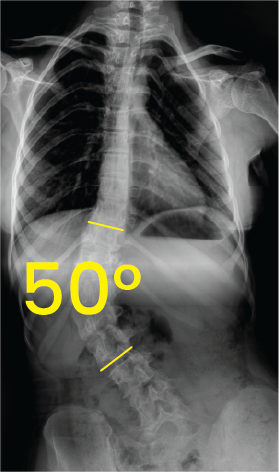

Göğüs ve bel omurgasını gösteren röntgen görüntüsü, omurga eğrilik açısı 50 derece olarak işaretlenmiş.Torakal omurga röntgeninde 38 derece skolyoz açısı ve omurgada metal vida yerleşimi.

Bel omurgasında 33 derecelik eğrilik gösteren skolyozlu insan göğüs ve karın röntgeni.Göğüs bölgesinde 17 derece eğiklik gösteren omurga röntgeni görüntüsü.